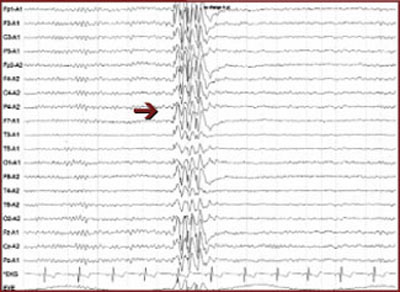

EEGs: EPILEPTIFORM ACTIVITY INDICATES POTENTIAL FOR SEIZURES

On an EEG, epileptiform activity is seen as spikes or sharp waves and indicates potential for epileptic seizures.

• Focal epileptiform activity is consistent with seizures of focal origin (e.g., simple partial, complex partial, or partial onset seizure with secondary generalization into tonic-clonic seizure).

• Generalized epileptiform activity is consistent with seizures of generalized onset (e.g., absence, myoclonic, or primary generalized tonic-clonic seizure).

Interictal spikes (between seizures) are consistent with, but not diagnostic of, seizures and epilepsy. An ictal discharge (rhythmic, persistent epileptiform activity) on an EEG accompanied by a clinical change in behavior is diagnostic of a seizure.

Focal epileptiform activity

Generalized epileptiform activity